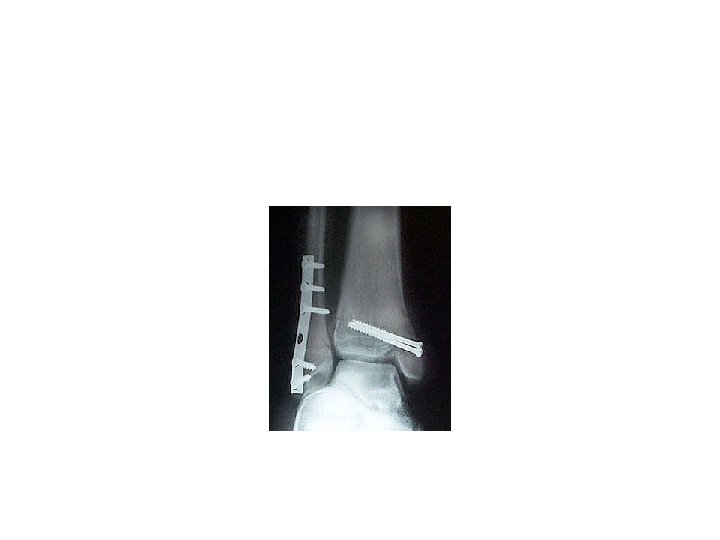

Open reduction 1 -displaced intra articular indications 2 -unstable Fr 3 -avulsion Fr 4

Open reduction 1 -displaced intra articular indications 2 -unstable Fr 3 -avulsion Fr 4 -Displaced pathologic Fr 5 - only operation indication 6 -Salter 3, 4 7 -compartment syn. 8 -NONUNION

Difinitive 1 -DEBRIDMENT 2 -FRACTURE TREATMENT A-INTERNAL FIXATION B-EXTERNAL FIXATION 3 - SKIN